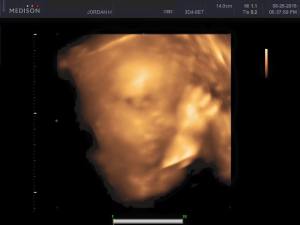

Baby Facts: We had our 3D/4D ultrasound this week. IT WAS AMAZING! Worth every penny. We confirmed baby is in no doubt A GIRL! (Good thing too…I didn’t want to return all the pink). We also got to see her adorable little face, which made me tear up a little bit. It amazes me how the body turns something so tiny into a little human in just 40 weeks.

Anyways, baby has some chubby cheeks already, as you can see. She also is already facing the correct way for her arrival into the world. The funniest moment is seeing how tight she is getting in there, our little goof was getting a bit too close to my belly and ended up squashing her nose a couple of times. (lol)